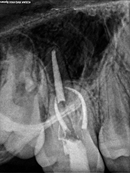

Root Canal Cases